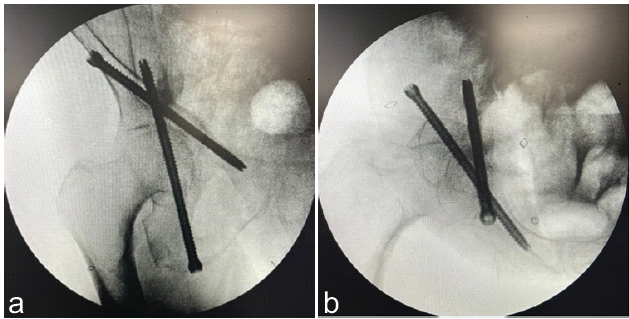

The patient was placed in the supine position following induction of general anesthesia. A small flat bump was placed directly under the midline of the patient’s sacrum to slightly elevate the patient’s pelvis relative to the bed. A standard surgical time-out was performed. Navigation reference guide pins were percutaneously inserted into the left ilium, and initial intraoperative O-arm imaging was used to confirm appropriate visualization of the acetabular corridors. A small incision was made, and dissection was carried down to the bone in the usual fashion. Utilizing a navigation-assisted cannulated guide, a guidewire was inserted for the 8.7 mm iFuse TORQ TNT screws (SI-Bone, Santa Clara, CA) in an antegrade fashion along the anterior column under CT-navigated guidance and confirmed to be safely positioned on a repeat O-arm spin. After safe confirmation of the screw in the osseous fixation pathway, a 140 mm iFuse TORQ TNT screw was inserted with satisfactory placement confirmed on C-arm fluoroscopy. A second guidewire was placed in a retrograde fashion along the posterior column using the same technique, with O-arm imaging used to confirm proper positioning before screw placement. A 150 mm TNT screw was placed across the posterior column. Final fluoroscopic and O-arm images confirmed stable fixation with no cortical breaches as seen in Fig. 2a and b.

Figure 2: (a and b) Intraoperative fluoroscopy 2 views showing both the anterior column (140 mm) screw and posterior column (150 mm) screw.